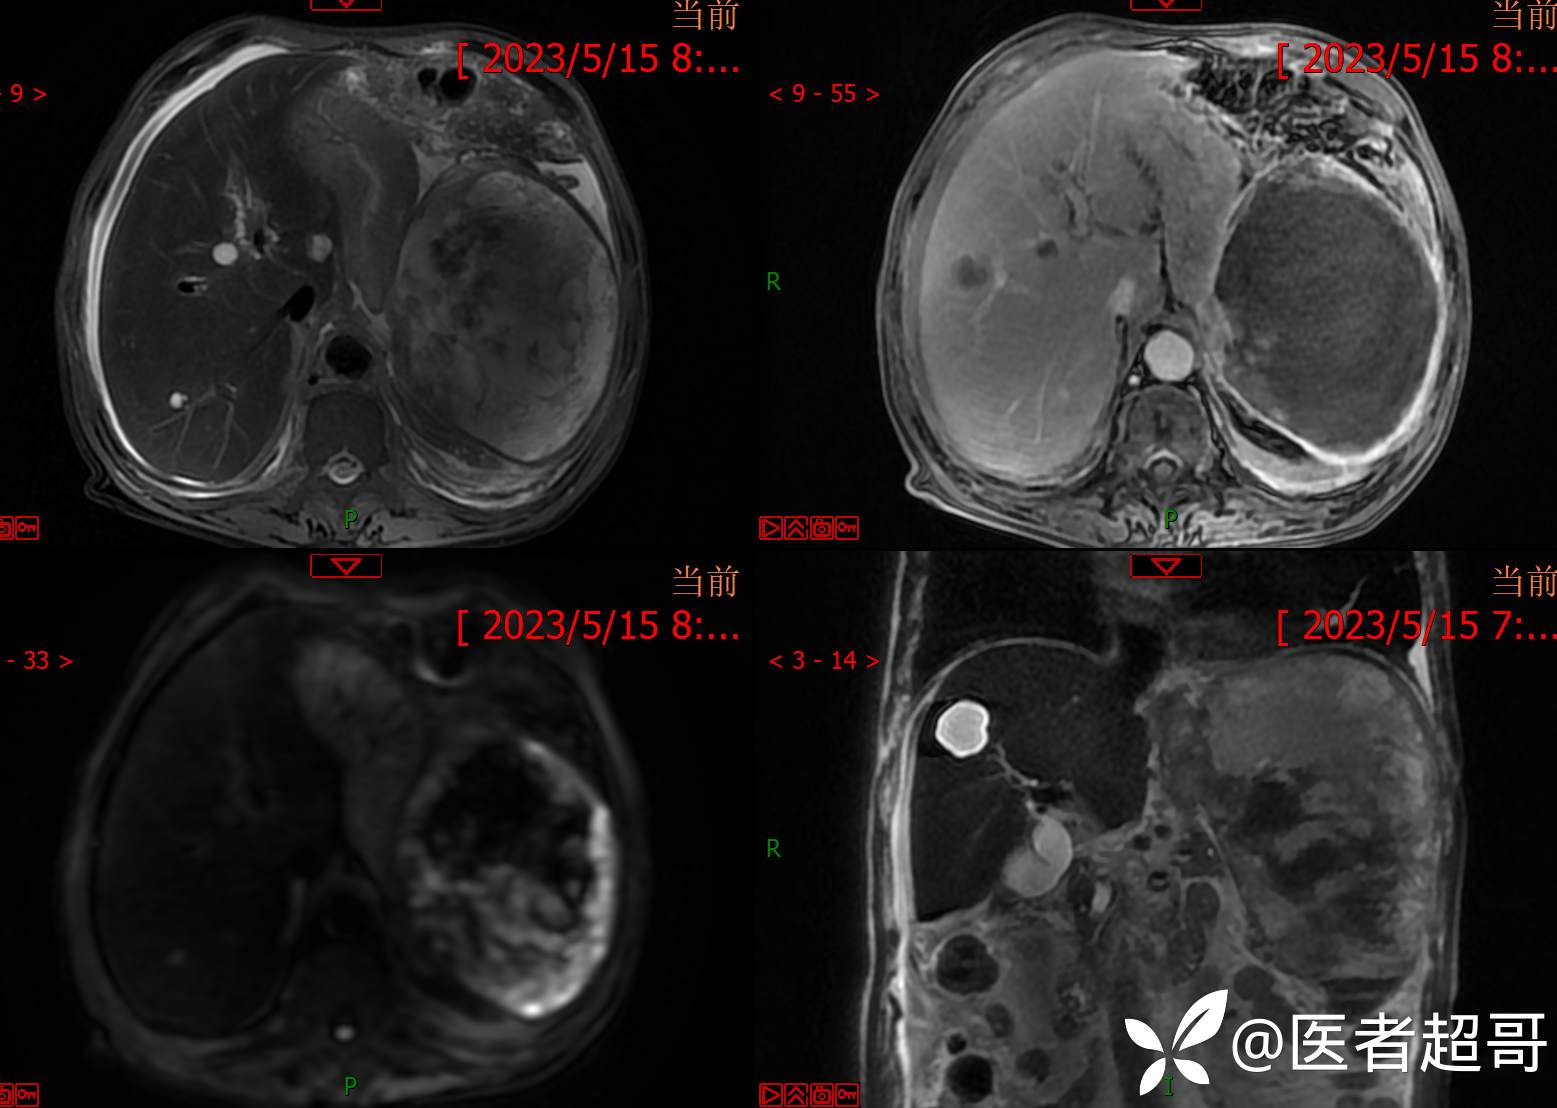

简要病史:左侧胸部疼痛不适5天就诊,临床初步诊断“肋软骨炎”。

两次穿刺显示阴性。